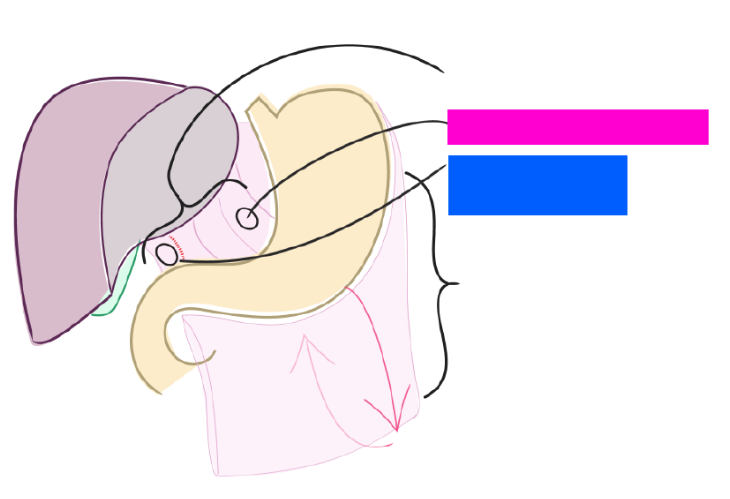

Liver

Lesser omentum

Hepatoduodenal ligament

blue box

Hepatogastric ligament

pink box

Greater omentum